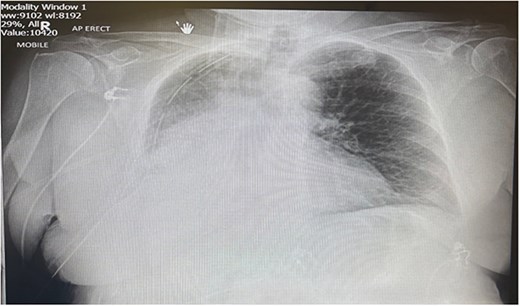

Postoperatively the patient required supplemental oxygen of 4 liters per minute that escalated to high flow nasal canula with 60 liters per minute. A chest x-ray depicted a right sided collection and collapse (Fig. 1). A computed tomography (CT) of the thorax was requested due to concerns from the chest x-ray and increased oxygen demand to maintain patient oxygen saturations between 88–92%. The CT confirmed a right sided moderate collection with secondary collapse and atelectasis of the lung suggestive of postoperative hemorrhagic changes (Fig. 2).

Portable chest X-ray Day 2 postoperatively. Chest X-ray depicts right middle and lower zone consolidation with associated pleural effusion.